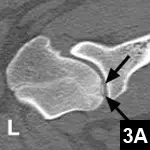

Comments: CT was performed to confirm the lesions. Figures 3A and 3B are images reformatted into the sagittal plane, showing the distinctly abnormal ossification of the subchondral bone in both humeral heads with an osteochondral fragment (Figure 3A, arrows) adjacent to the left humeral head (osteochondritis dissecans).

Figure 3A. The reformatted sagittal CT image of the left shoulder; the arrows are pointing to the osteochondral fragment.

Figure 3B. The reformatted sagittal CT image of the right shoulder; the arrowhead is pointing to the subchondral defect.